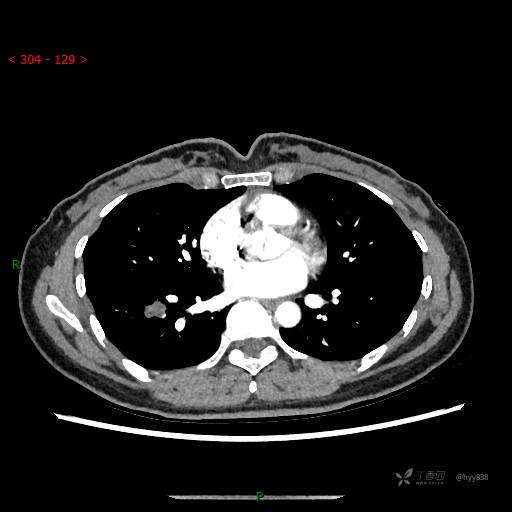

增强动脉期

静脉期